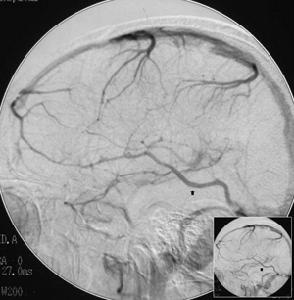

8.腦血管造影成人一次5-10ml(每1ml中含碘300mg)。